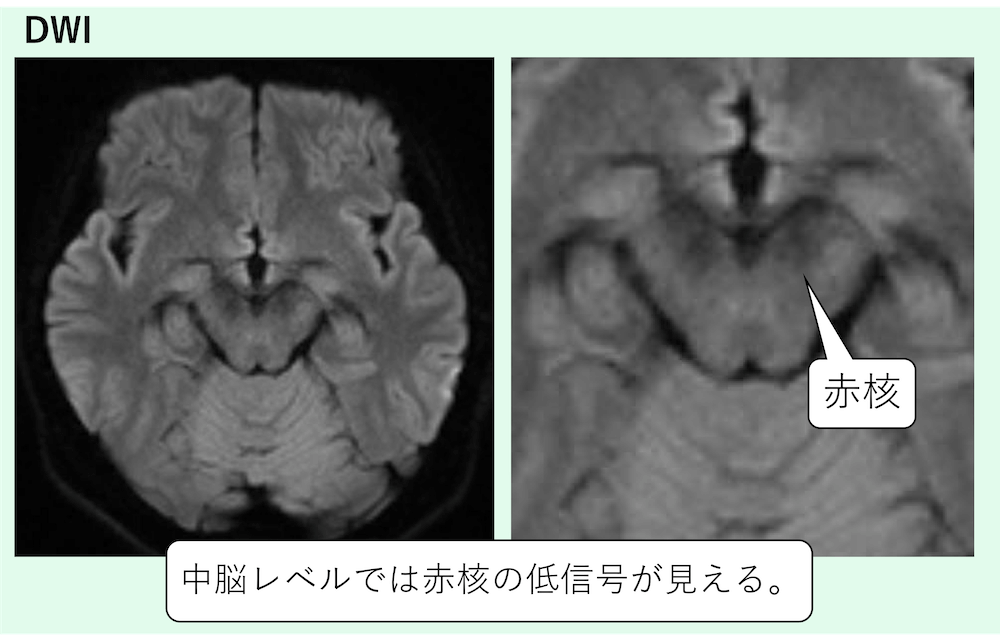

2)脳幹の核(鉄・メラニン・局所磁化率で黒く見えやすい)

- 赤核(red nucleus)

中脳レベルでは赤核の低信号が見えます。